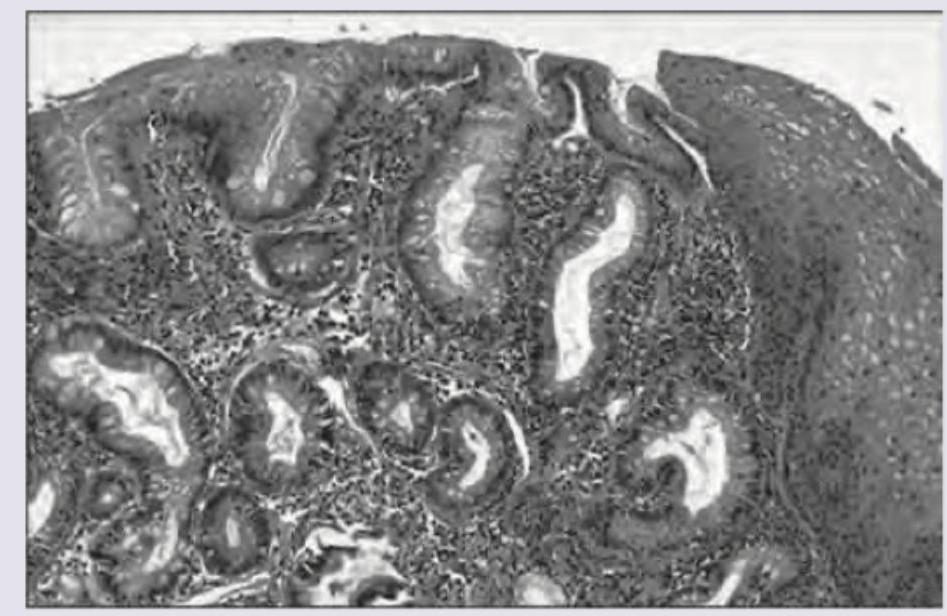

A 15-year-old patient develops intussusception for which he was operated and a segment of intestine showing multiple polyps was resected. The microscopy showed the following pathology. What is the likely diagnosis?

Explanation: ***Hamartomatous polyps*** - The patient's age (15 years), presentation with **intussusception**, and the presence of **multiple polyps** are highly suggestive of a hamartomatous polyposis syndrome, such as Peutz-Jeghers syndrome [1,2]. - **Hamartomatous polyps** are non-neoplastic malformations of normal tissue components, often leading to complications like intussusception in younger individuals [2]. *Tubulovillous polyps* - These are **adenomatous polyps** with a significant risk of malignant transformation, typically seen in older adults. - While they can cause symptoms, **intussusception** in a 15-year-old with multiple polyps is less characteristic of tubulovillous adenomas. *Inflammatory polyps* - These polyps are usually a result of chronic inflammation, such as in **inflammatory bowel disease**. - They are generally not associated with **intussusception** as a primary presentation in a young patient with multiple polyps. *Adenocarcinoma* - **Adenocarcinoma** is a malignant tumor and is rare in a 15-year-old, especially as multiple primary lesions causing intussusception. - While polyps can transform into adenocarcinoma, the initial presentation in a young patient points more towards a **benign polyposis syndrome** [1,2]. **References:** [1] Kumar V, Abbas AK, et al.. Robbins and Cotran Pathologic Basis of Disease. 9th ed. The Gastrointestinal Tract, pp. 813-815. [2] Kumar V, Abbas AK, et al.. Robbins and Cotran Pathologic Basis of Disease. 9th ed. The Gastrointestinal Tract, p. 813.